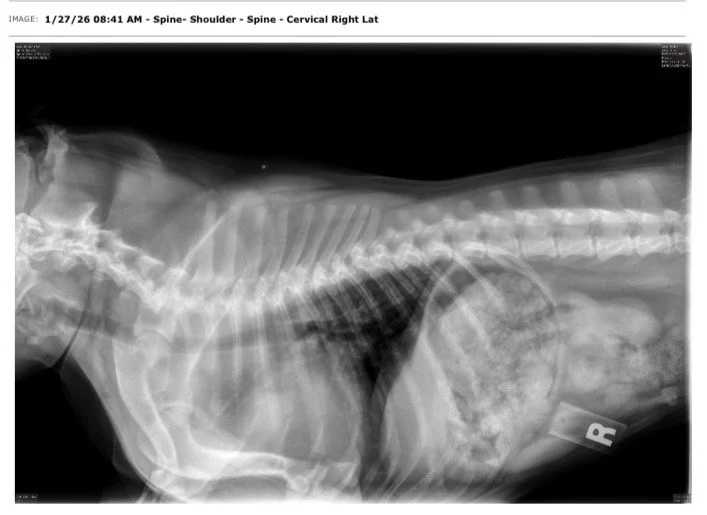

Testés OFA de la race pour Hanches, Coudes, Rotules, Colonne Vertébrale, Coeur & Yeux.